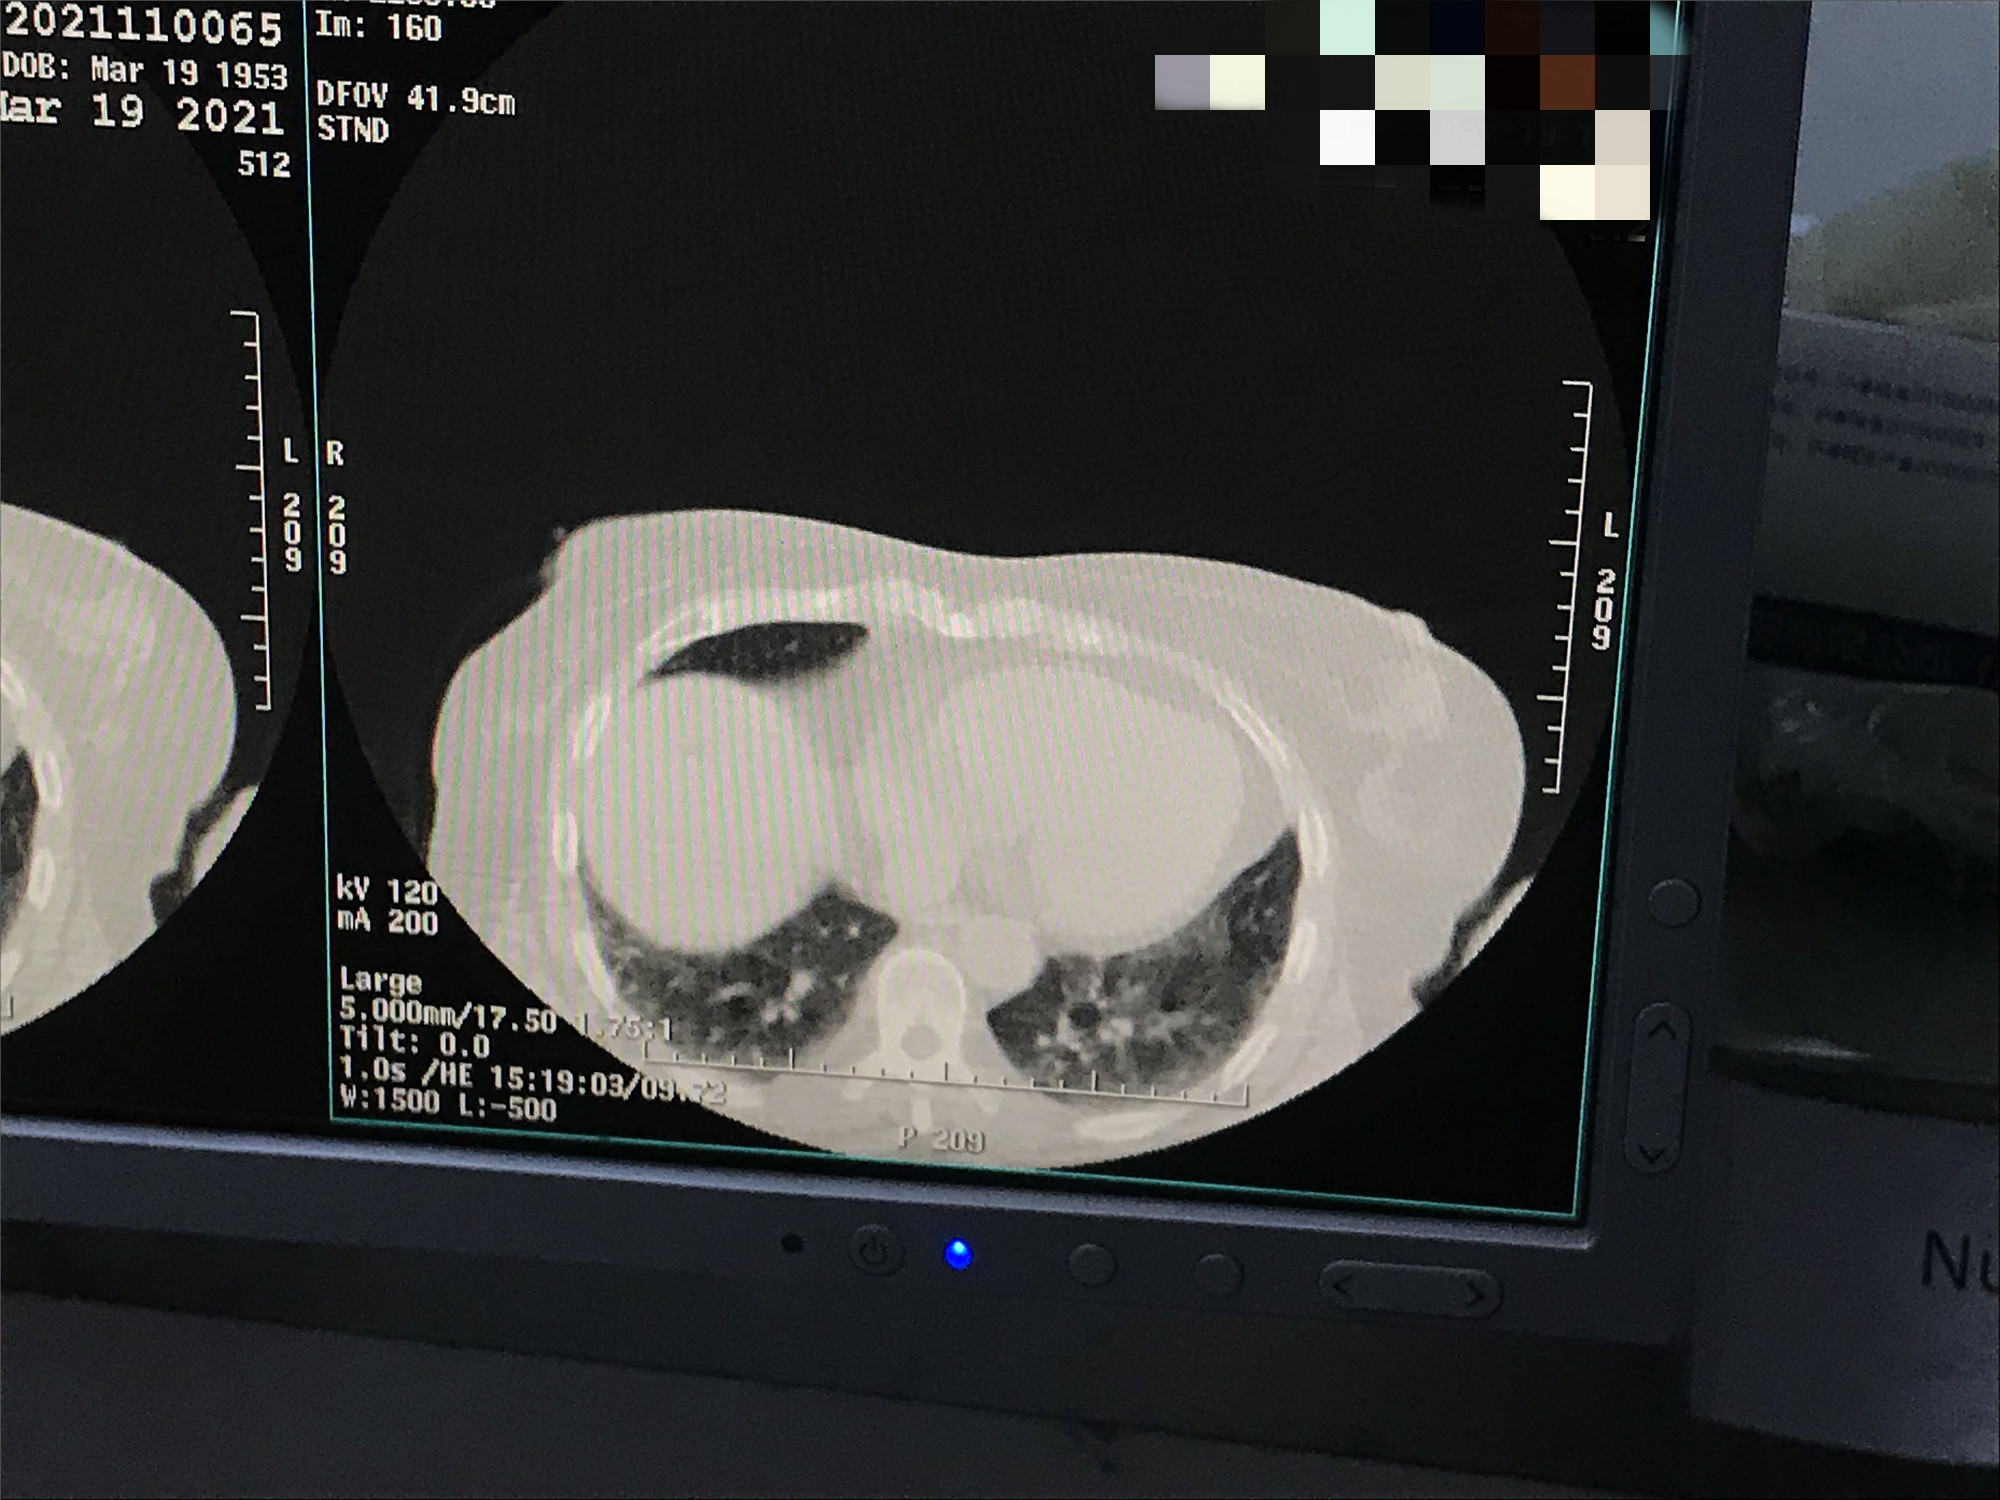

2021年3月份肺部氩氦刀手术

发布人:美国氩氦刀技术官方网站    发布时间:2021/9/22 15:44:51